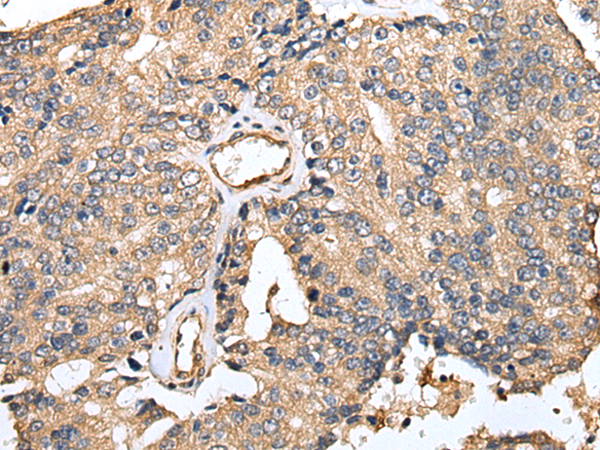

IHC positive control:

Human prostate cancer and Human tonsil